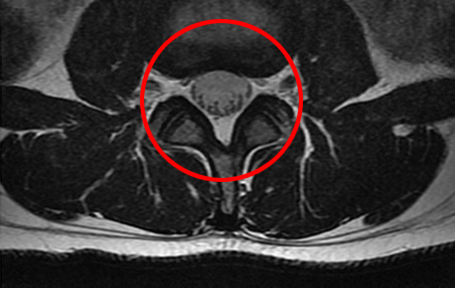

• 모커리한방병원 MRI로 본 정상적인 척추관 이미지

정상적인 척추관

척추관협착증은 척추 뼈와 인대, 후관절, 디스크 등이 전체적으로 모두 퇴행되어 척추관이 좁아지고 신경압박이 발생하는 질환입니다.